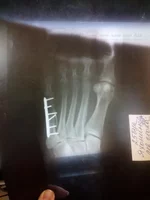

Перелом со смещением

Сломал кость, которая сразу за мизинцем левой ноги.

Вправили, сделали гипсовую шину. Прошла неделя и контрольный снимок показал незначительное смещение. Врач сказал, что все в пределах нормы. Опухоль спала и перестала держать кость. И если еще через неделю смещение окажется сравнительно большим, возникнет необходимость хирургического вмешательства. Но раз уже немного смещено, может нет смысла ждать еще неделю?

И существует ли альтернативная возможность как-нибудь выпрямить кость без хирургического вмешательства?